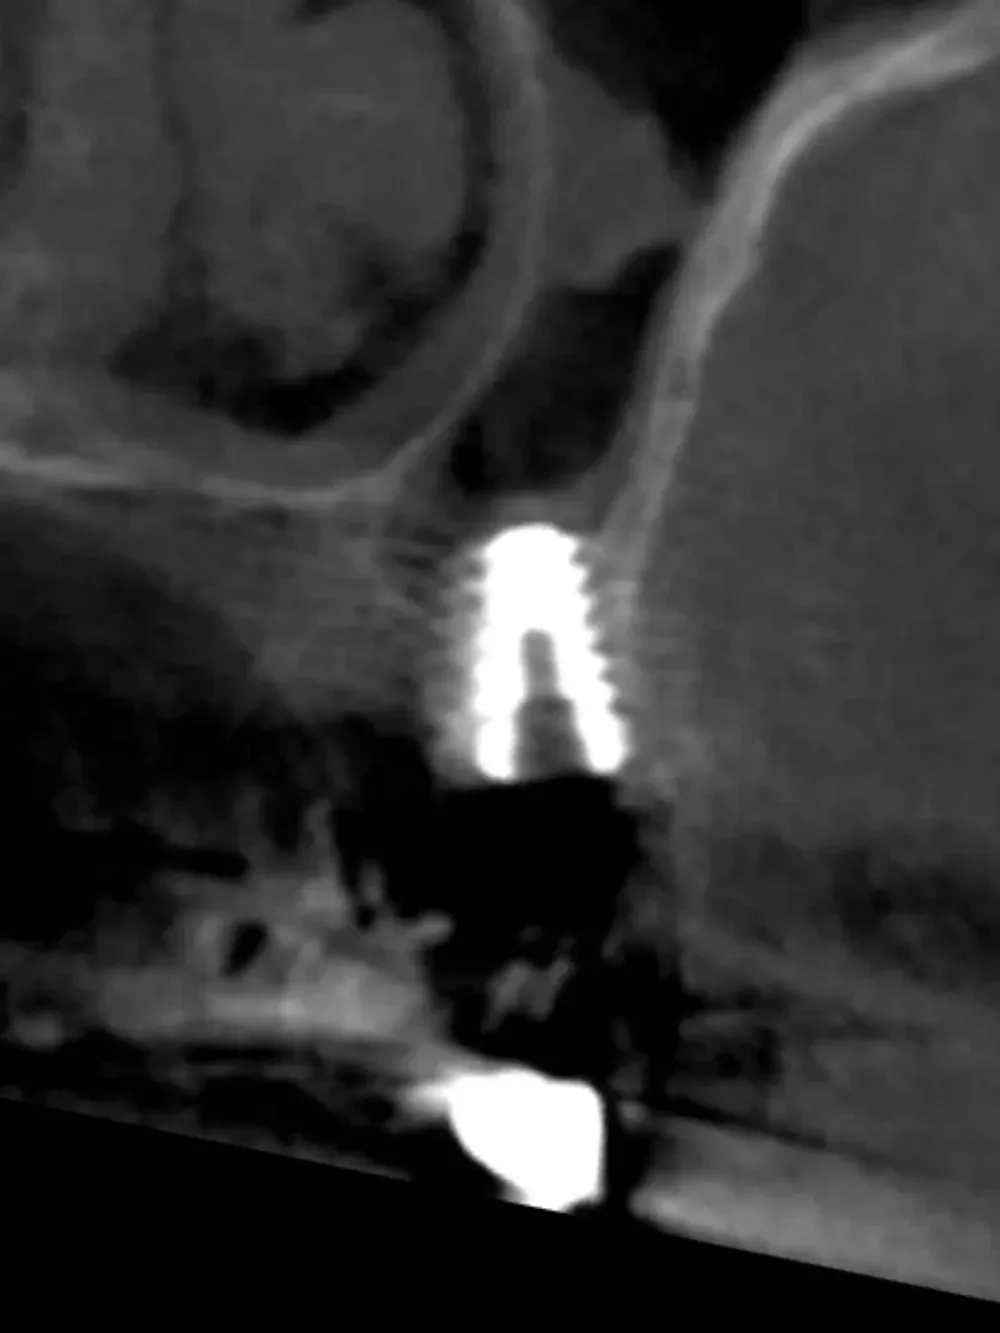

La CBCT intraoperatoria ha confermato la corretta posizione tridimensionale degli espansori e il raggiungimento della corticale del pavimento del seno in zona 2.5. In caso di dubbi sulla posizione e nel corso di interventi delicati come questo, questo ausilio strumentale è di fondamentale importanza. Ma non è sempre necessaria. L’esposizione, per quanto contenuta, dev’essere sempre ridotta al minimo, compatibilmente con la sicurezza chirurgica.

Sezione espansore sito 2.4

Sezione espansore sito 2.5

CBCT Post-op: Impianto in posizione 2.4 infracrestale che ha raggiunto la posizione di ingaggio corticale corretta

CBCT Post-op: Impianto in posizione 2.5 infracrestale con sollevamento della corticale del pavimento del seno